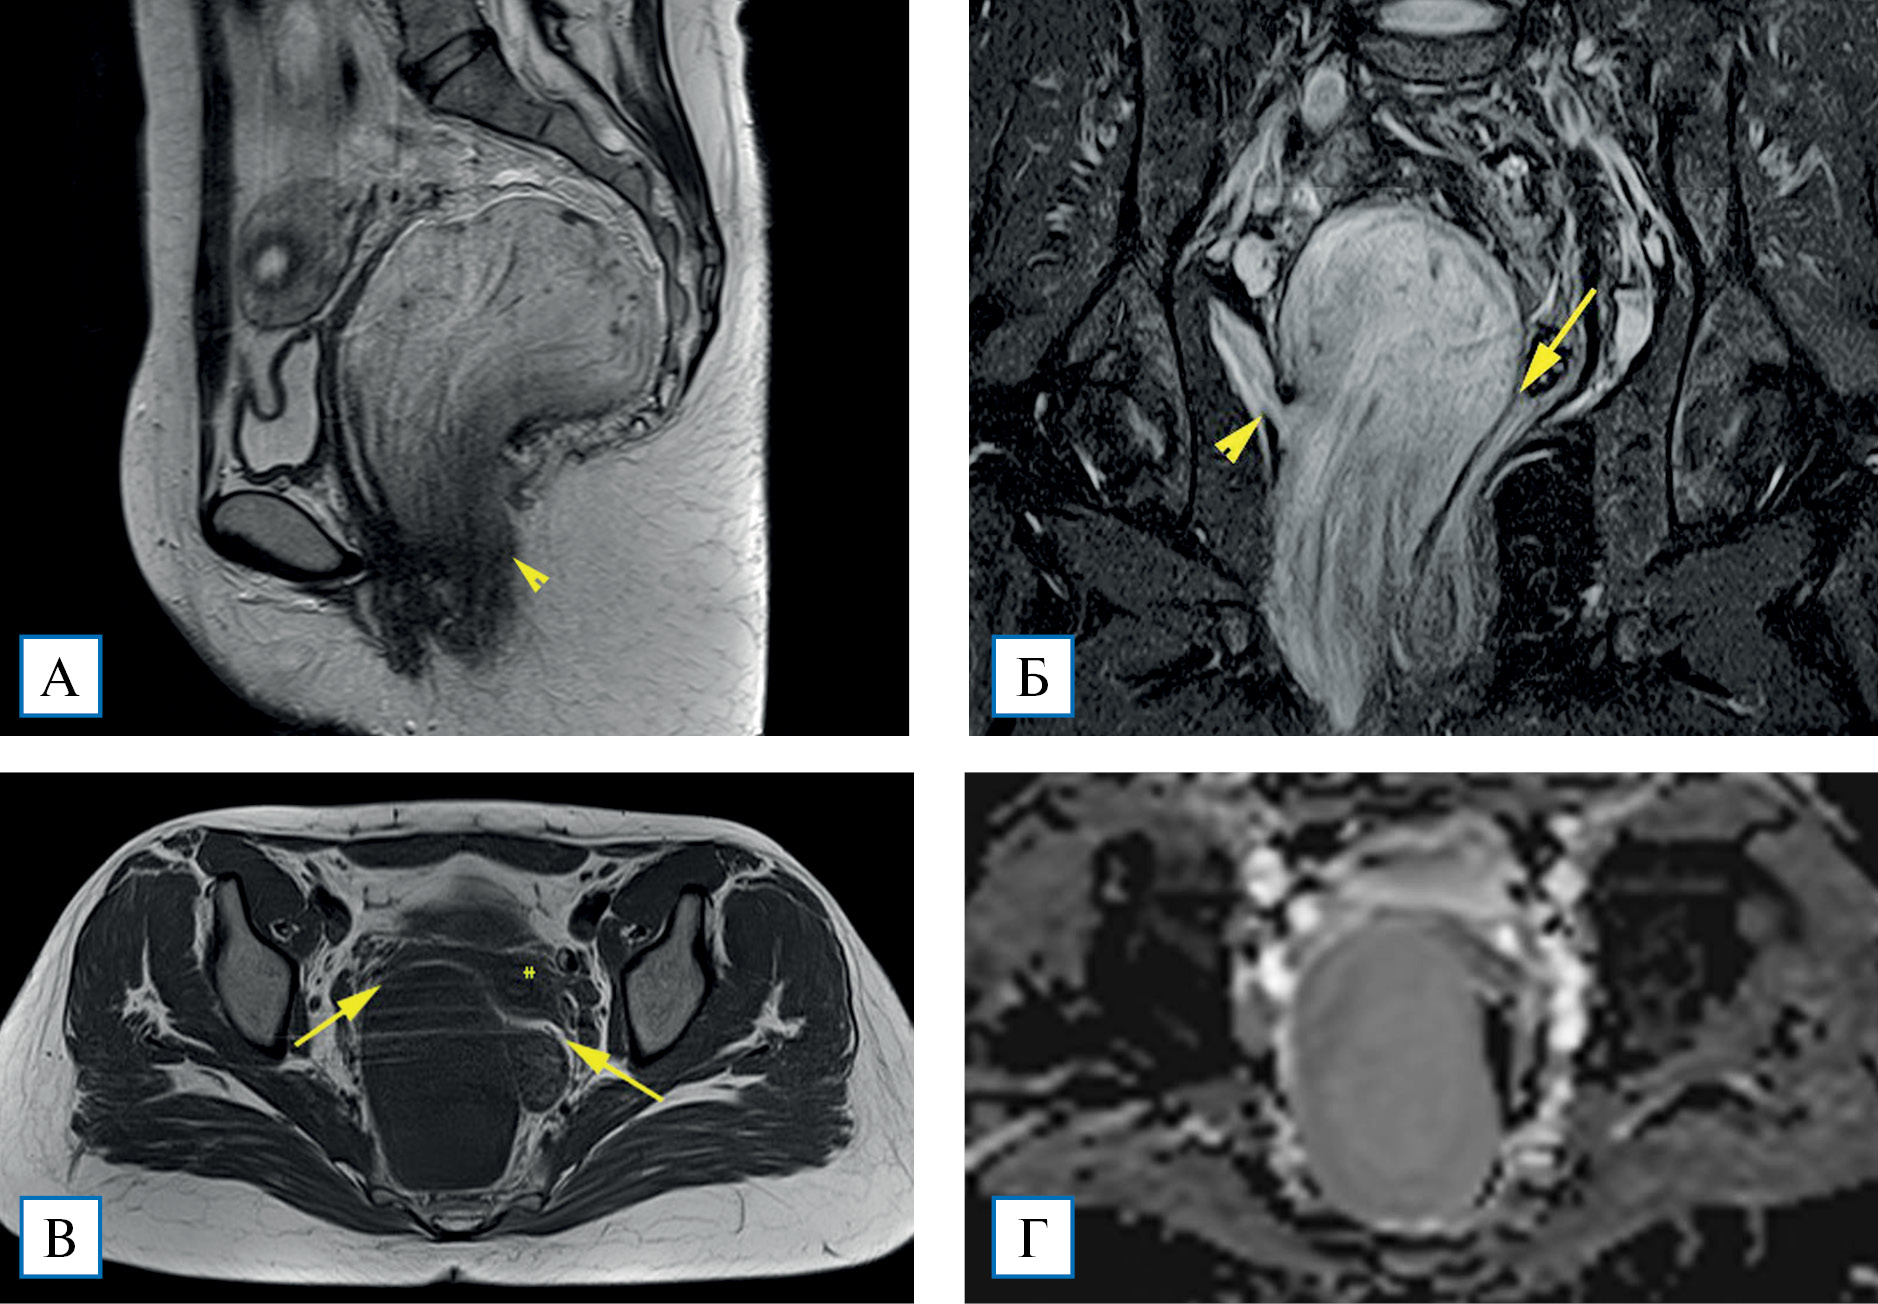

На 4-й день госпитализации выполнено МР-исследование: в малом тазу справа определяется объемное образование размером 70×70×145 мм с четким наружным контуром. На Т2-ВИ МР-сигнал по интенсивности выше, чем от миометрия, но ниже, чем от жидкости. Структура неоднородная за счет тонких беспорядочных протяженных волокнистых включений. На Т1-ВИ опухоль однородно гипоинтенсивная. Жироподобных включений, участков выпадения МР-сигнала, соответствующих кальцинатам, не прослеживалось. При получении диффузионно-взвешенных изображений данных за ограничение диффузии молекул воды не отмечено. Опухоль оттесняет в стороны прилежащие органы малого таза без признаков их инвазии. Нижний полюс опухоли выглядит нечетким, распространяется к m. levator ani (мышца, поднимающая задний проход) справа и в клетчатку правой седалищно- анальной ямки, инфильтрируя их (рис. 2).

Рис. 2. МР-томограммы малого таза, Т2-ВИ в сагиттальной плоскости (А), Т2-ВИ с подавлением сигнала от жира в корональной плоскости (Б), Т1-ВИ в аксиальной плоскости (В), изображение с картой исчисляемого коэффициента диффузии в аксиальной плоскости (Г)

Примечание. Объемное образование вовлекает m. levator ani справа (А, Б, наконечники стрелок). Между образованием, маткой, придатками матки справа и прямой кишкой прослеживаются жировые прослойки (Б, В, стрелки). Исчисляемый коэффициент диффузии от образования составляет около 2300 мм/с2 (Г).